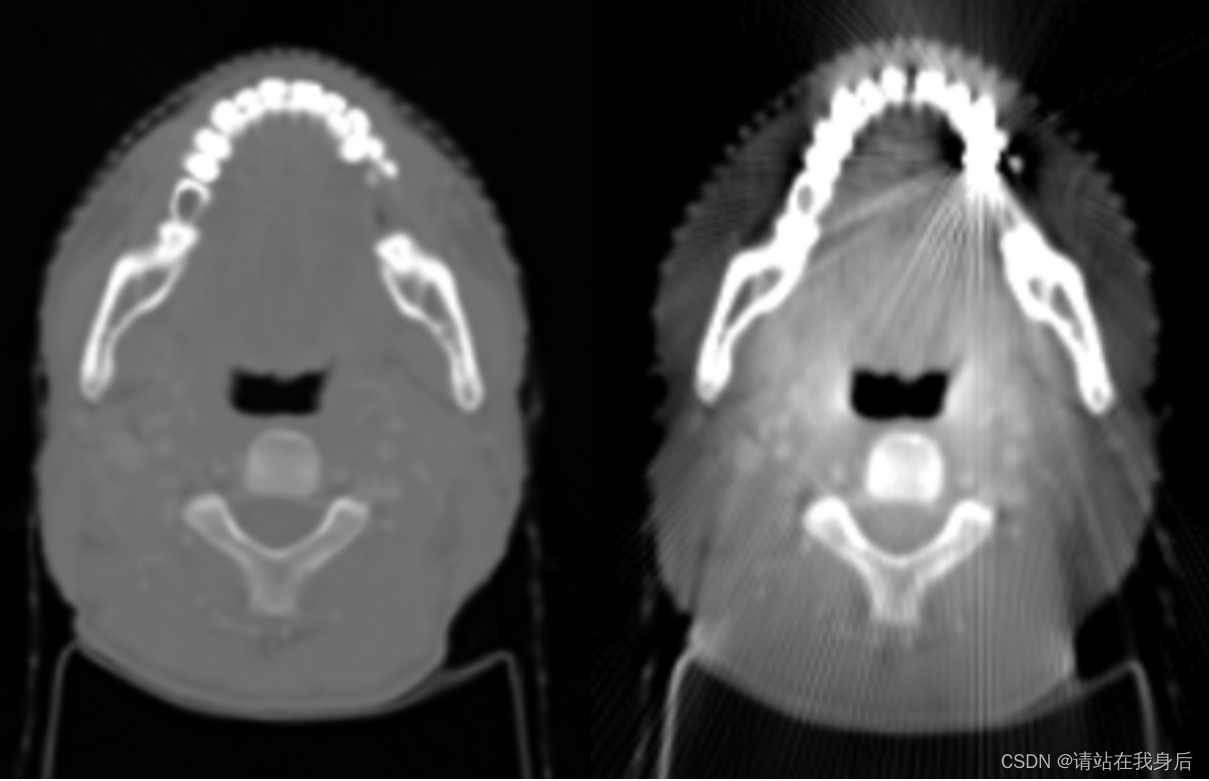

贴张演示图

plt.figure();plt.imshow(withMA[0], cmap='gray');plt.title('模拟金属伪影的CT图')

plt.show()